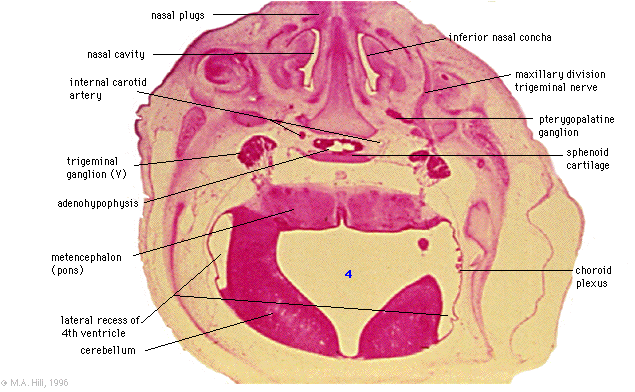

Trigeminal nerve and ganglion, with maxillary division emerging. Pterygopalatine ganglion. Nasal conchae. Adenohypophysis.